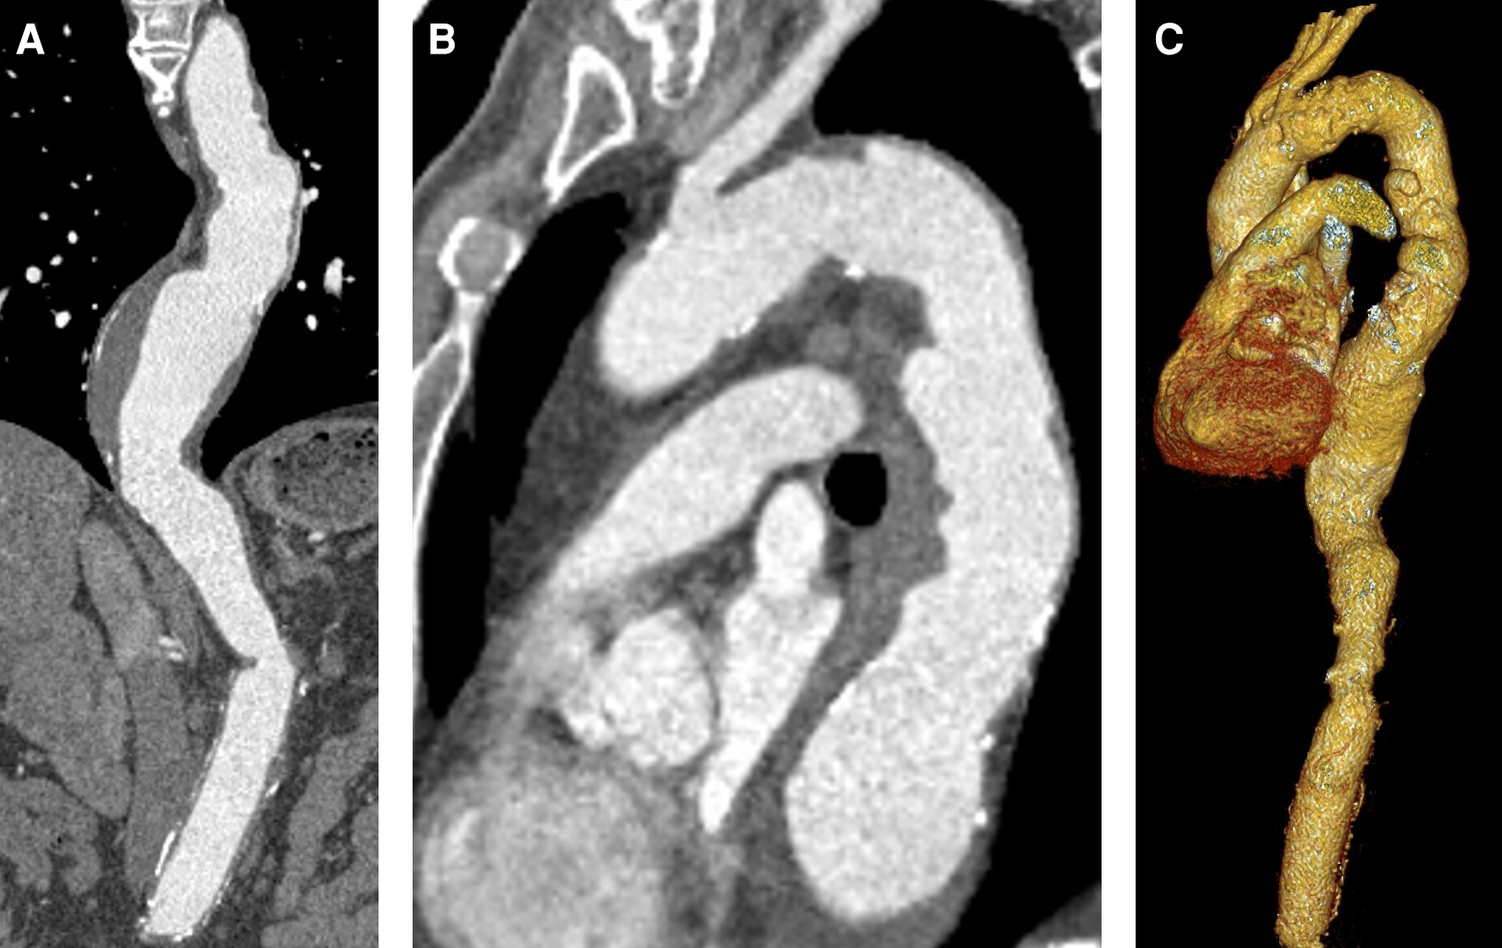

Figure 1

Preoperative CTA. (A) Descending aortic aneurysm with 63 mm diameter. (B) Proximal landing zone distal to the left subclavian artery (30 mm). (C) 3D reconstruction.

An 80-year-old male patient underwent elective computed tomographic angiography (CTA) scan for checkup of a known thoracoabdominal aneurysm. Nine years before, he received open surgical repair of juxtarenal abdominal aortic aneurysm with reimplantation of the left renal artery. Results of the recent CTA (SOMATOM Definition Flash, Siemens®, Erlangen, Germany) are depicted in Figure 1 and showed a thoracic aortic aneurysm with 63 mm of the descending aorta. According to the current guidelines, TEVAR was recommended to prevent aortic dissection or rupture (2). Therefore, he was referred to a local vascular surgery department for TEVAR. Proximal landing zone diameter distal from the left subclavian artery was estimated to be 30 mm. At this point of time, the patient was free of symptoms. Due to the involvement and reimplantation of the left renal artery, the left kidney was already atrophic for several years, resulting in chronic renal failure stage 3b with a glomerular filtration rate of 45 ml/min. In addition, he suffered from long-term arterial hypertension with fourfold antihypertensive medication, non-insulin-dependent type 2 diabetes and dyslipidemia, both treated with oral medication, as well as an adequate substituted hypothyroidism. There was no anamnestic evidence of genetic or hereditary aortic diseases as well as similar familiar cases.